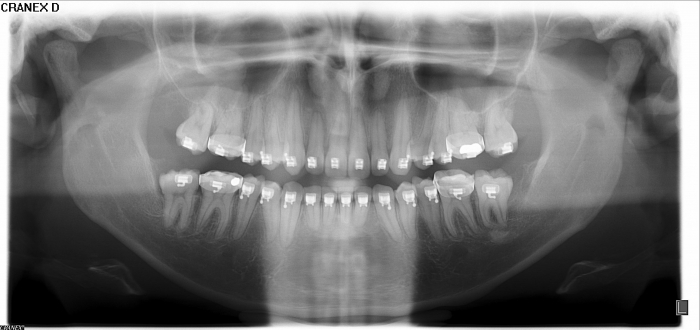

Rx Panorâmico inicial  - Clínica Cliniface

Rx Panorâmico inicial